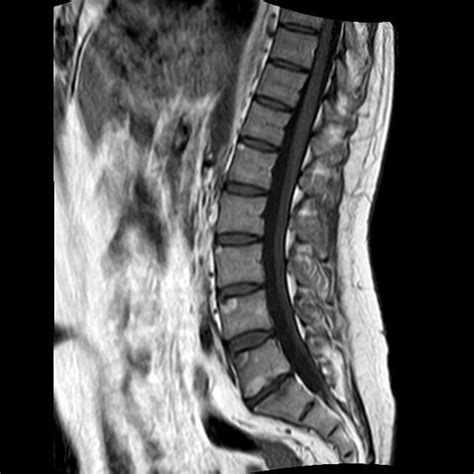

Spondylitis (inactive Romanus lesions) in a 39yearold patient with

Web healing response to these inflammatory erosions appears radiographically as reactive sclerosis in the same location, which is known as the shiny corner sign 3. Ragnar romanus, a swedish general surgeon, and sven yden, a swedish radiologist, described this eponymous lesion in a paper in 1955. A small break in a bone, seen with a thurstan holland sign. [4] it is most easily diagnosed using mri, compared to conventional radiography. Web the shiny corner sign is observed due to ostetitis in inflammatory arthropathies, most classically in ankylosing spondylitis. Web the shiny corner sign is a medical sign which may refer to: Romanus lesions of the spine (shiny corner sign) vertebral body squaring; Shiny corner sign of c6 inferior vertebral endplate. Web early spondylitis is characterized by small erosions at the corners of vertebral bodies with reactive sclerosis: Web the shiny corner sign is a spinal finding in ankylosing spondylitis, representing reactive sclerosis secondary to inflammatory erosions at the superior and inferior endplates (corners on lateral radiograph) of the vertebral bodies which are known as romanus lesions.

Web early spondylitis is characterized by small erosions at the corners of vertebral bodies with reactive sclerosis: [4] it is most easily diagnosed using mri, compared to conventional radiography. Web the shiny corner sign is observed due to ostetitis in inflammatory arthropathies, most classically in ankylosing spondylitis. Shiny corner sign of l3, l4 and l5 superior vertebral endplates. A location of sclerotic density associated with a romanus lesion. Web early spondylitis is characterized by small erosions at the corners of vertebral bodies with reactive sclerosis: Web t1 sagittal t2 axial t2 shiny corner sign of c6 inferior vertebral endplate. Shiny corner sign of c6 inferior vertebral endplate. This disambiguation page lists articles associated with the title shiny corner sign. A small break in a bone, seen with a thurstan holland sign. Web healing response to these inflammatory erosions appears radiographically as reactive sclerosis in the same location, which is known as the shiny corner sign 3.